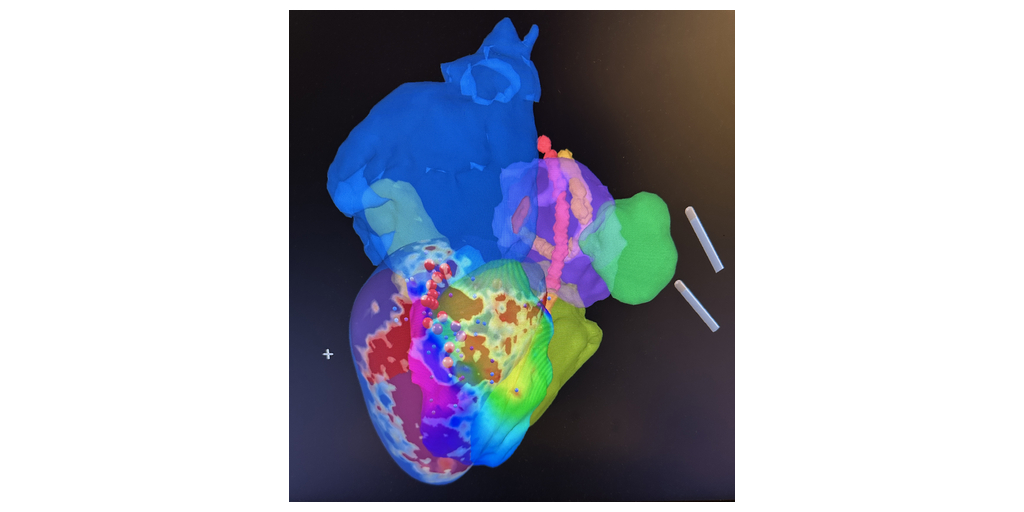

Il team del Centro medico universitario di Amsterdam, illustrato qui, ha eseguito l'intervento di ablazione della TV dopo precedenti esperienze di interventi di ablazione del flutter atriale e del complesso ventricolare prematuro (PVC) guidati da RMN in tempo reale e dal NorthStar® Mapping System di Imricor.